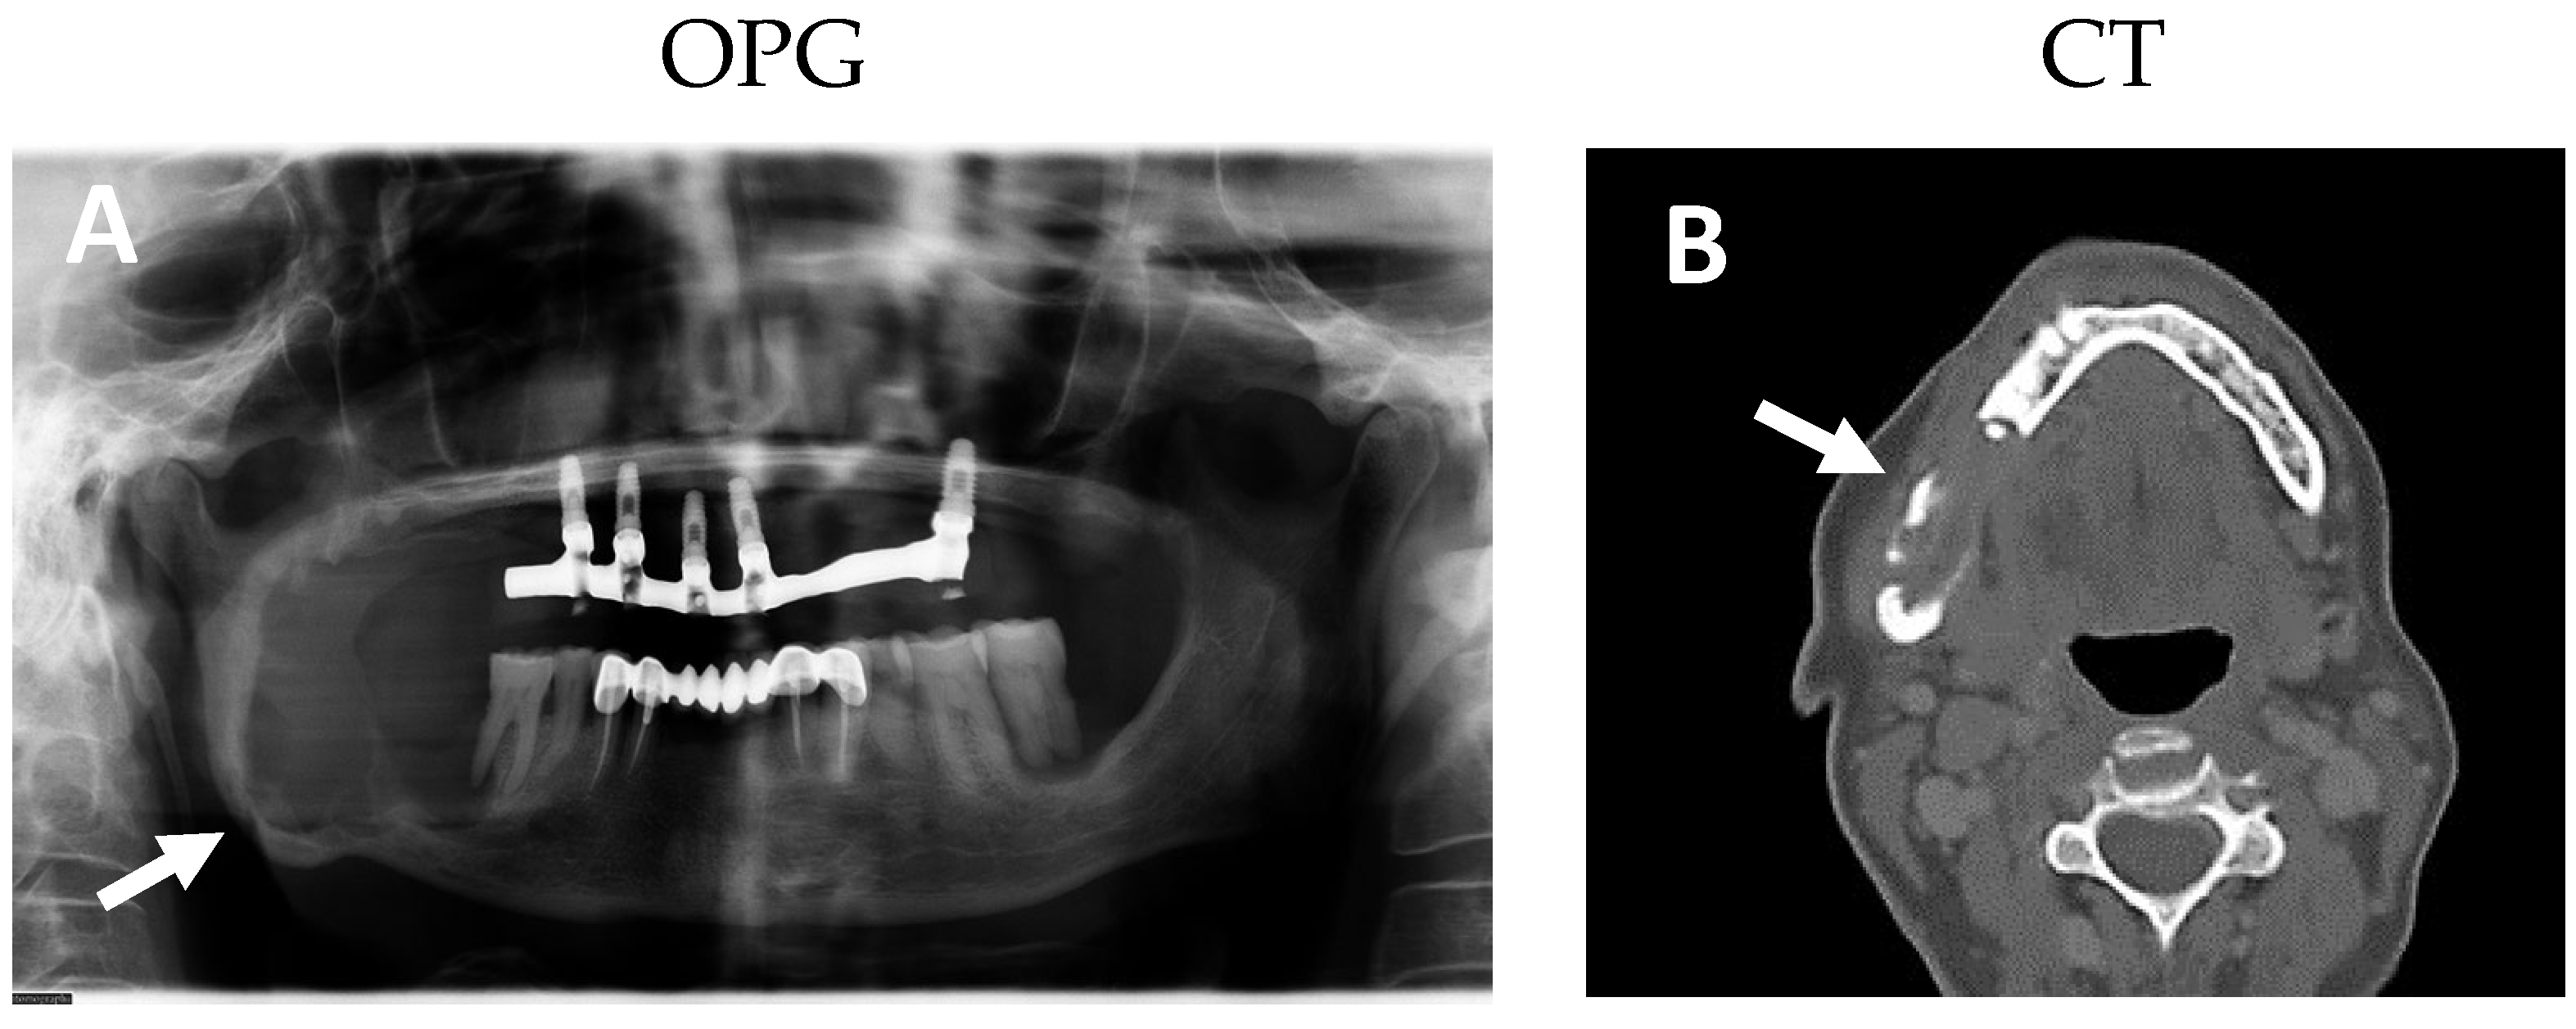

2.1. Clinical and Histological Manifestations of the Tumors

4.2. Magnetic Resonance Imaging

4.3. Positron Emission Tomography-Computed Tomography